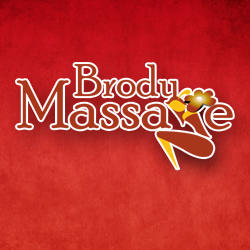

Multi Modality Imaging Features Distinguish Pancreatic Carcinoma

Multi Modality Imaging Features Distinguish Pancreatic Carcinoma

Multi Modality Imaging Features Distinguish Pancreatic Carcinoma